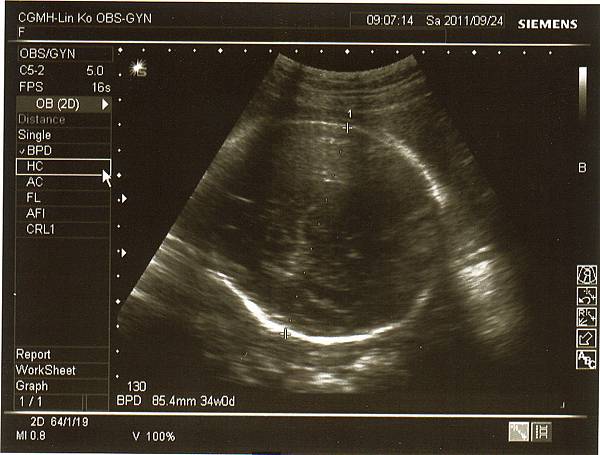

醫生說很重要的兩條動脈~

兔妹妹的腎臟(不過我實在看不太懂)~